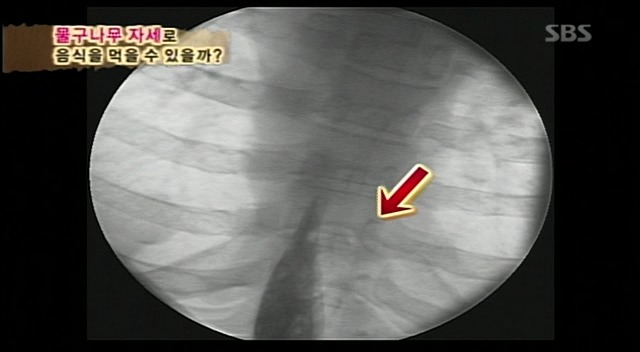

예성이가 먹었던 음식에 비하여 훨씬 빠른속도로 위를 향해 감.

위까지 빠르게 도착하는듯 싶었으나...

액체에 가까워 그런지 빠르게 역류함..

유부남 이성민씨는 열심히 침삼키며 연동운동하고

계속 침을 삼키며 연동운동하니

요플레는 무사히 위에 도착!